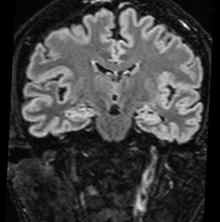

Diagnosticul clinic al MC se bazează pe următoarele 3 elemente clinice: comă profundă cu un scor Glasgow de 3, abolirea tuturor reflexelor trunchiului cerebral, absenţa respiraţiei spontane, după un test de hipercapnie. Cele două examinări paraclinice utilizate in completarea diagnosticului clinic de MC sunt angiografia-CT cerebrală multislice sau electroencefalograma (EEG). Dopplerul transcranian (TCD) este util pentru alegerea momentului realizării lor (1-4)

ACTMS trebuie efectuată: după o perioadă de 6 ore de la diagnosticul clinic, la un pacient stabil hemodinamic (media presiunii arteriale > 65 mmHg) (1) . Cronologic, oprirea sistemului circulator interesează in primul rând ramurile corticale ale arterele cerebrale medii, apoi ramurile proximale a poligonului Willis și în final circulaţia vertebro-bazilară. Efectul întârziat asupra circulației posterioare s-ar explica prin rolul protector al tentoriului cerebelului împotriva creșterii presiunii intracraniene. Absența opacifierii venelor cerebrale interne în ACT constituie cel mai precoce, mai sensibil și mai specific semn al MC demonstrând stopul circulator în etajul supratentorial (2)

• Studiul opacifierii ramurilor corticale ale arterelor cerebrale medii (M4) drepte și stângi și a venelor cerebrale interne drepte și stângi (Fig.1).

• Un scor egal sau mai mare de 3 confirmă stopul circulator intracerebral. In acest caz, concluzia examinării este: „stop circulator intracerebral” care vine în sprijinul diagnosticului clinic de moarte cerebrală sau aspect ACT compatibil cu moartea cerebrală

În cazul opacifierii unilaterale a uneia dintre cele două artere cerebrale medii, diagnosticul de MC poate fi afirmată dacă este absentă opacifierea venelor cerebrale interne (Fig,2).